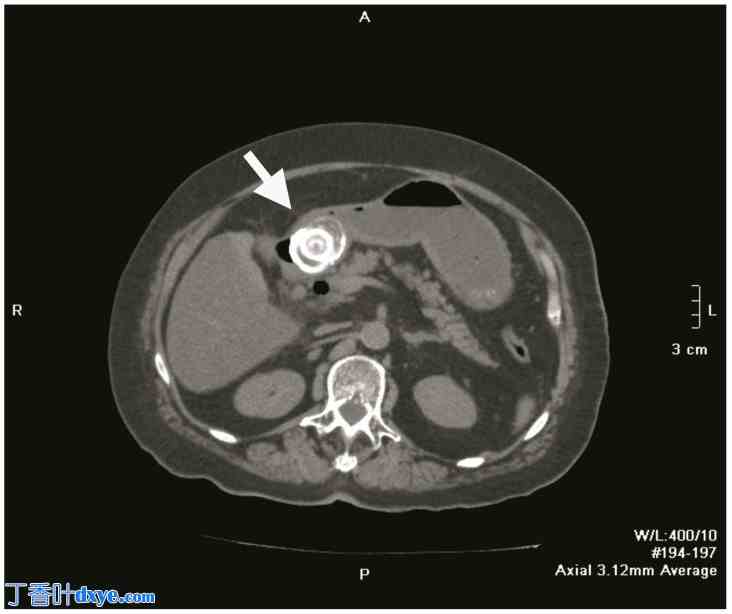

图 1.

上腹部轴向非造影 CT 图像显示十二指肠球内嵌有一颗大的胆结石(白色箭头),这是布弗雷综合征的特征性表现;胆结石阻碍了胃液流出,并导致明显的胃扩张。在膨胀的胃内观察到气液平面。